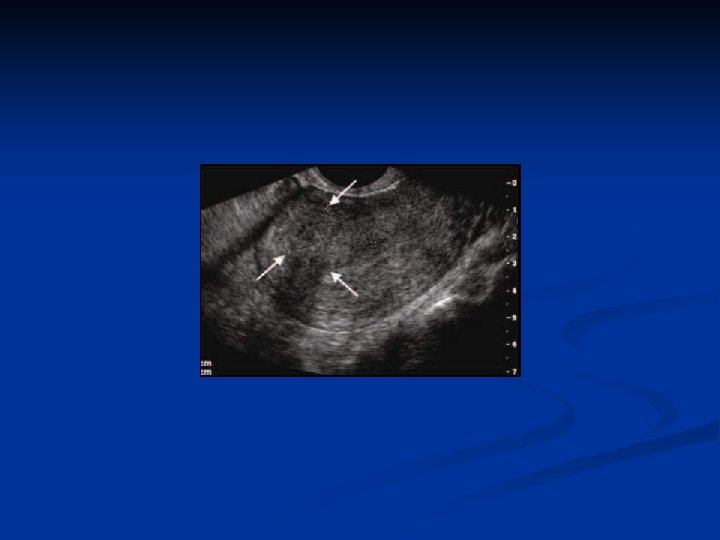

Adenomyosis n n Is defined by the presence of endometrial glands and stroma within the myometrium Can be diffuse or localised ( adenomyosis) Incidence is 20% Pathogenesis is unkown n Might be sec to postpartum endometritis because of the endom line break down An arrest of Mullerian cells in the myometrium and later de nova endometrial gland development Animal models suggest PRL and FSH stimulates growth

Adenomyosis n Symptoms and signs n n n Menorrhagia Dysmenorrhea Treatment n n Hysterectomi Gn. RHa